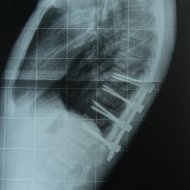

Scheuermann kifozu olan bir hastanın ameliyat öncesi ve sonrası fotoğrafı görülüyor.